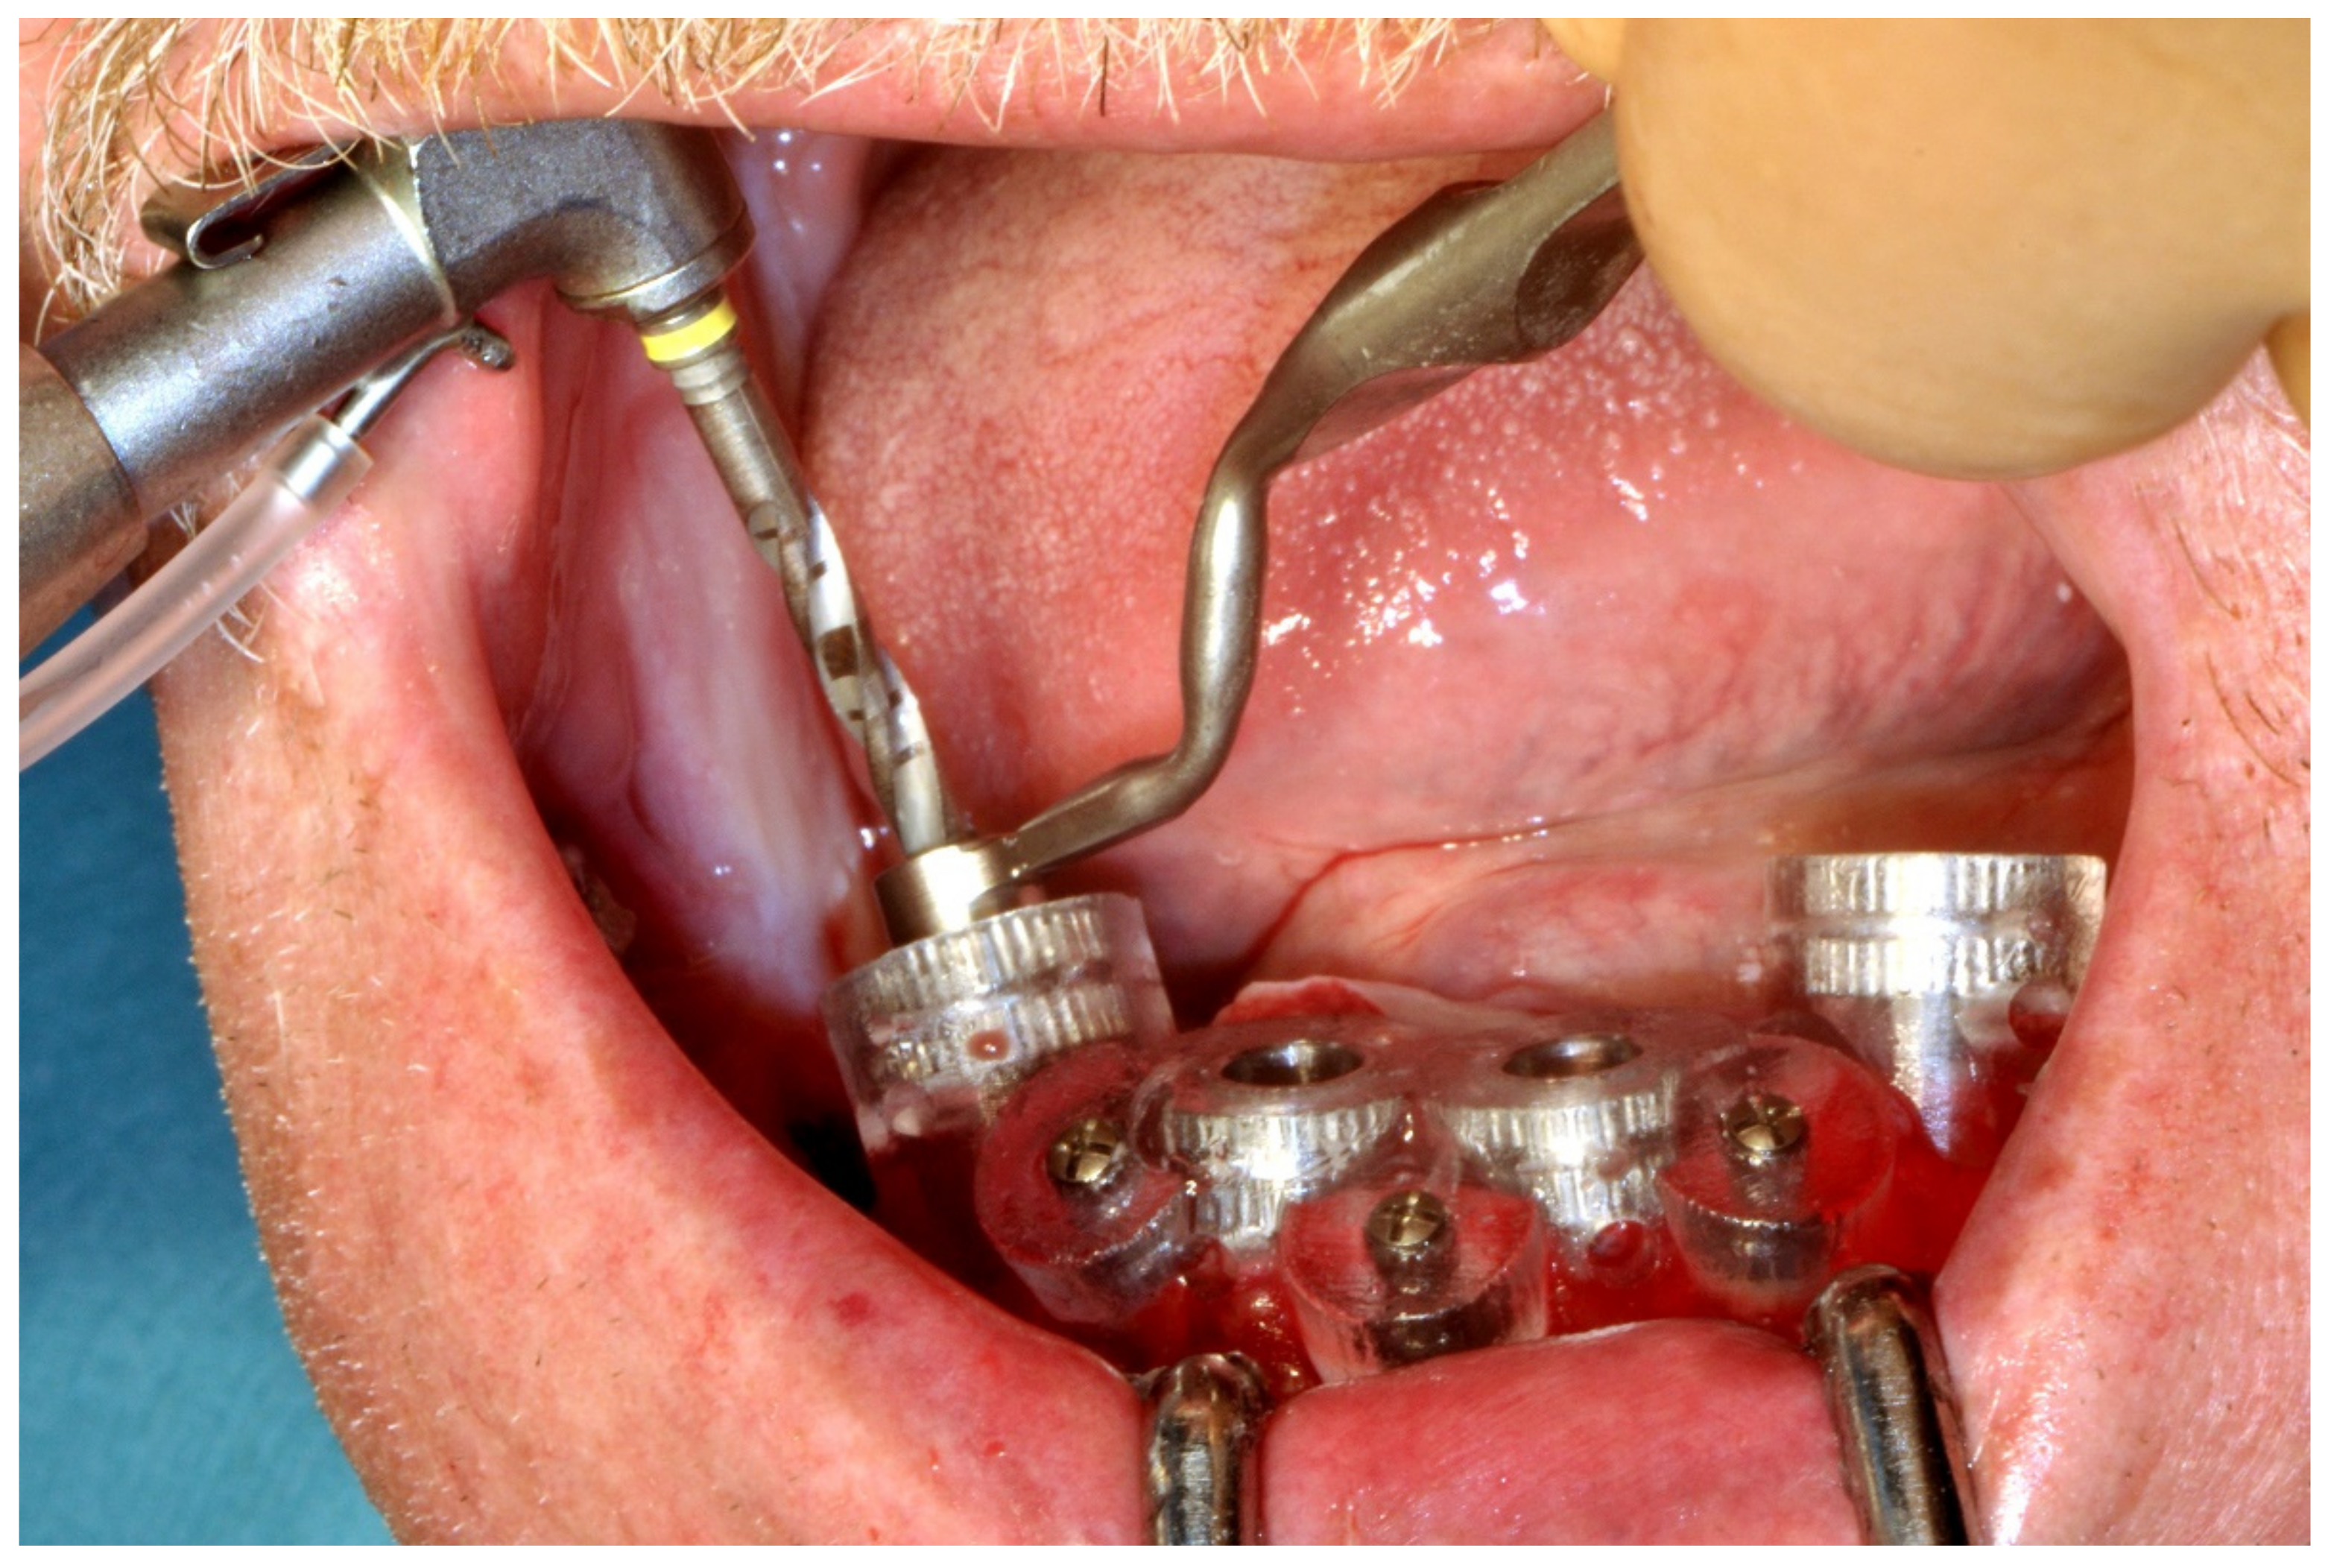

6.3.4. Intra-Operative Documentation: